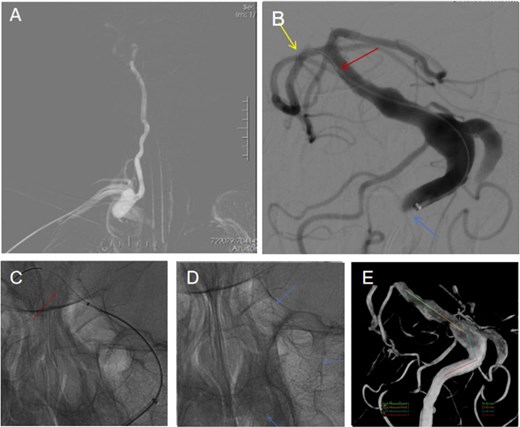

Via the right radial sheath, a distal access catheter was advanced through the upper limb artery, right subclavian artery, and right vertebral artery to the V3 segment. An XT27 stent delivery microcatheter was then inserted through the distal access catheter and guided by a 0.014-inch microwire to the P2 segment of the right posterior cerebral artery. Next, a Nuva flow-diverting stent (model TJED-D-6.5-35) was released through the XT27 catheter (Fig. 2). Once the stent is released, it can be extended to a length of 56 mm within a 6.0-mm-diameter blood vessel, according to the manufacturer. Thus, a single 35-mm device was sufficient to cover the clinically relevant ectatic segment while ensuring safe distal and proximal landing zones. The distal landing zone of the flow-diverting stent was located at the distal basilar artery, approximately 0.8 mm from the origin of the superior cerebellar artery; the proximal end of the stent was positioned within the proximal V4 segment of the vertebral artery, about 2 cm proximal to the dural ring.

A flow-directing close-mesh stent was implanted from the right vertebral artery to the basilar artery (A) Angiography was performed through the right vertebral artery, and a flow-diverting dense-mesh stent was deployed. (B) Contrast image during the procedure showing the guidewire in the right posterior cerebral artery (yellow arrow); the tip of the stent catheter at the distal basilar artery (red arrow), which is also the distal landing point of the flow-diverting stent (red arrow); and the 5F distal access catheter at the distal vertebral artery (blue arrow). (C) Intraoperative findings. The leading end of the stent was opened through the XT27 stent catheter. (D) Cardiography after stent release shows deployment of the Nuva 6.5 × 35 (extendable to 56 mm) flow-diverting dense-mesh stent via the stent catheter (blue arrow). (E) On the basis of 3D vascular reconstruction, the expected coverage of the vertebrobasilar segment was 15.42 + 13.43 + 11.48 + 13.91 = 54.24 mm.